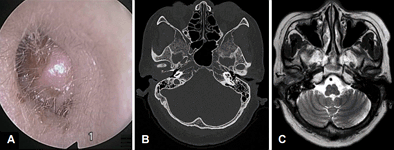

1. 62세 여자 환자가 3주 전부터 발생한 우측 이통과 청력저하를 주소로 내원하였다. 순음청력 검사상 우측 기도청력은 44 dB, 골도청력은 13 dB이었다. 환자의 이경(A), 측두골 전산화 촬영(B)과 자기공명영상(C) 소견은 다음과 같았다. 조직검사상 편평상피세포암종으로 확인되었고, cancer workup상 modified university of Pittsburgh TNM staging system이 T2N0M0일 때 가장 적절한 치료는?

답 ③

해설 외이도의 high-grade carcinoma의 경우 osseous EAC의 involving 또는 abutting 소견이 관찰되면 lateral temporal bone resection을 우선 고려하며, cartilaginous 또는 soft tissue invasion이 있는 경우 postoperative radiotherapy를 시행한다.